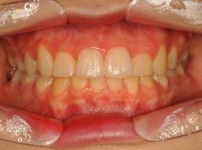

5

BEFORE

AFTER

클릭 해주세요.

전체치아교정

치아교정